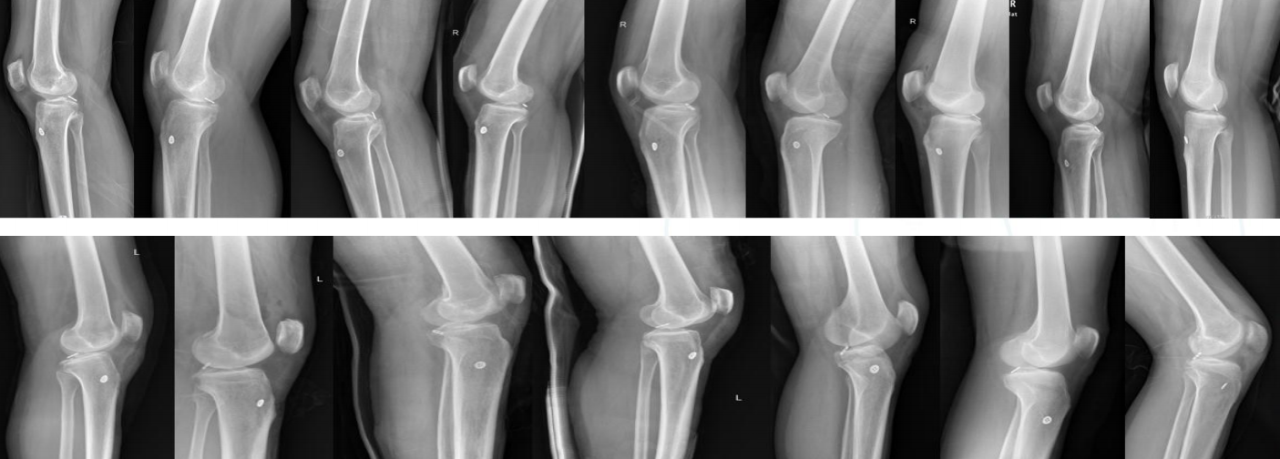

术后X线片